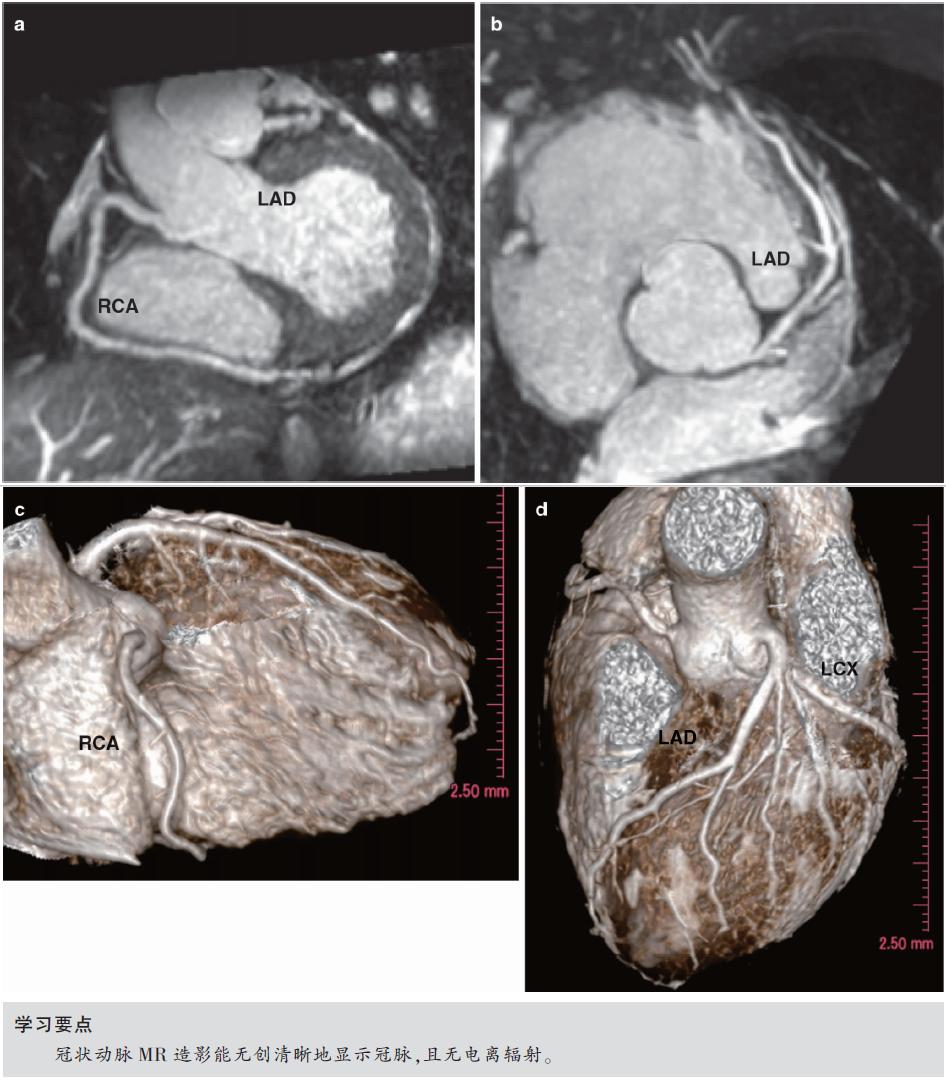

★ 冠状动脉MR造影(CMRA)是无创、无辐射的冠状动脉成像方法(图7.1)。

★ 全心自由呼吸三维CMRA可以全面显示心脏冠状动脉主干,可以在轴位图像上逐层观察。

图7.1 1.5T正常冠状动脉受试者,自由呼吸全心CMRA。采用1.5T MR获得非对比增强的三维CMRA图像,采用稳态自由进动(SSFP)序列、导航回波门控、T2预扫描、光谱预饱和反转恢复脂肪饱和(TR/TE,4.6/2.3ms;翻转角度,90°;SENSE因子4;FOV 280mm×280mm×120mm;采集矩阵256×256×80;重建矩阵512×512×160)。

(a)右冠状动脉(RCA)薄层最大强度投影(MIP)图像。(b)左主干和前降支(LAD)薄层MIP图像。(c)RCA的VR图像。(d)LAD和LCX的VR图像。